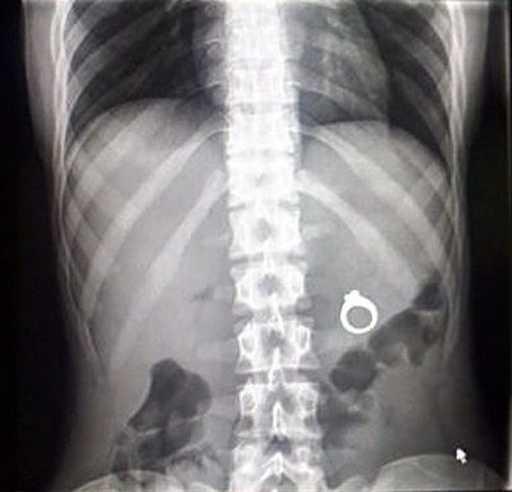

10. 「我朋友的儿子吞了雪花?」

一些奇怪的X光照片,看完整个人都不好了……-10.jpg